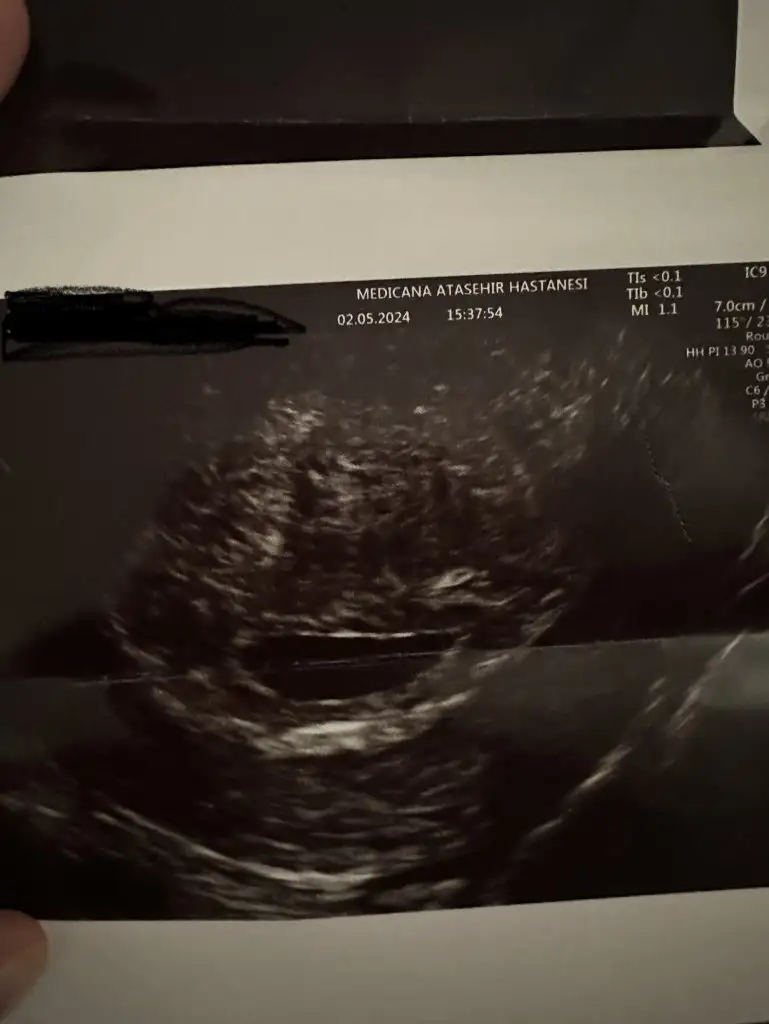

Ultrasonun kalitesi bile etkiliyor ya zamanı, görece daha eskiyse o bile duymanı engelleyebilir. Yolk sac vs görünmüştür belki ondan boş değildir demiştir kalbini ferah tutSelam kizlar ilk ultrasonuma 5+3 te girmistim kese gorunmustu dun 6+2 de tekrardan girdim tekrardan kese gorundu doktora cogu 6. Haftasinda kalp atisini duyuyo bende bebek henuz gorunmuyo bos gebelik mi acaba dedim hayir bos gebelik degik 5 6. Haftalarda kese gorunur 8. Haftada kalp atisi duyulur dedi ultrasonda biseyler gosterip bak yeni olusmaya basliyo dedi vajinal ultrason yapmadi ne oldugunu soramadin o an haftaya yine cagirdi benim durumumu yasayan var mi?